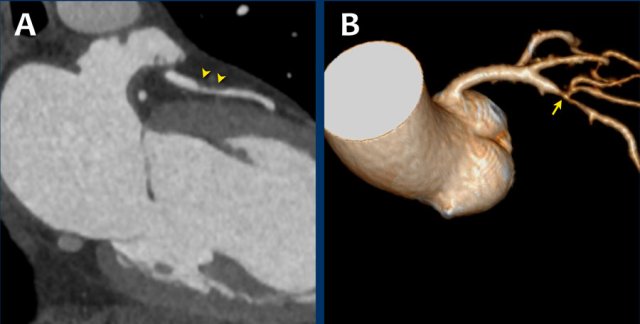

Same patient.

Double-oblique (A) and volume-rendered (B) images of the LAD showing the

location and the length of the plaque.

Also, the stenosis in the D2 branch of the LAD can be appreciated on the volume

rendered reconstruction.